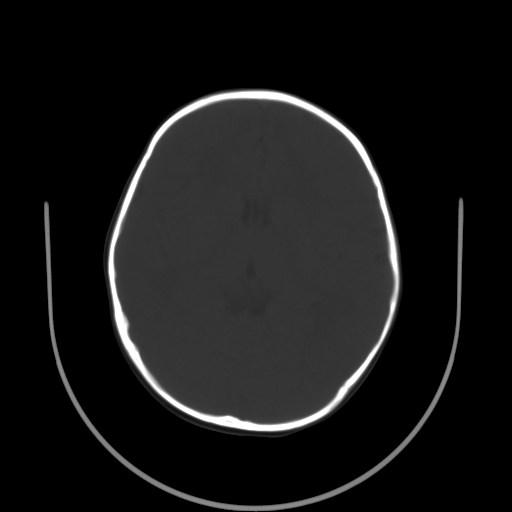

以下是引用拾荒者在2009-10-17 18:38:00的发言:[br]鼻面部皮下积气,右侧睑缘及眼球壁高密度异物影,左侧眼球壁晶状体内侧缘处是圆形低密度影。低密度异物?应提请眼科医生注意。